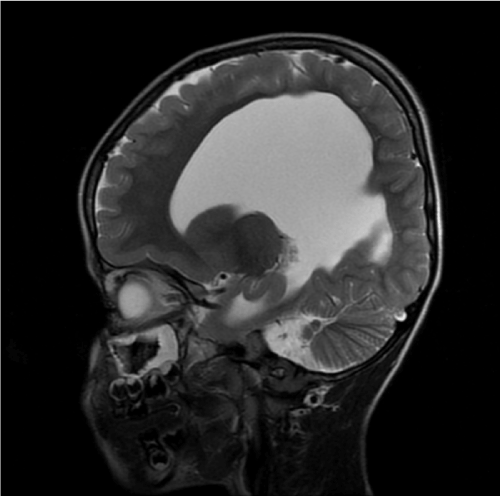

Figure 1. MRI shows the fusion of cerebellar hemispheres with absent vermis. The 4th ventricle is small and has diamond shaped

Figure 4. There is a fusion of cerebellar hemispheres with absent vermis, ventricular prominence without aqueductal stenosis and the absent septum pellucidum giving a mono-ventricle appearance

Figure 3. Coronal MRI show an absence of a vermis with continuous cerebellar white matter tracts and cortex across the midline